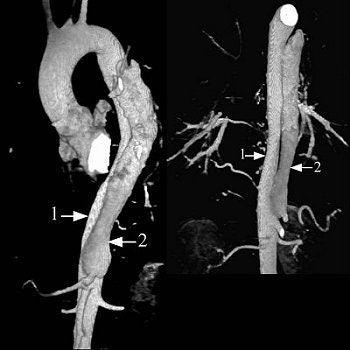

The initial entry site of Stanford B and its relationship with left subclavian artery (top images, both VR).